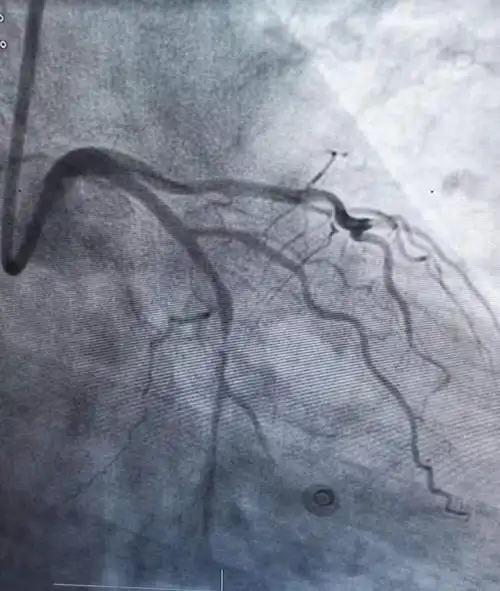

(造影可见冠状动脉严重狭窄伴斑块破裂)

冠状动脉狭窄

"是冠状动脉造影,它是一种介入性的检查,能直观心脏血管狭窄的情况